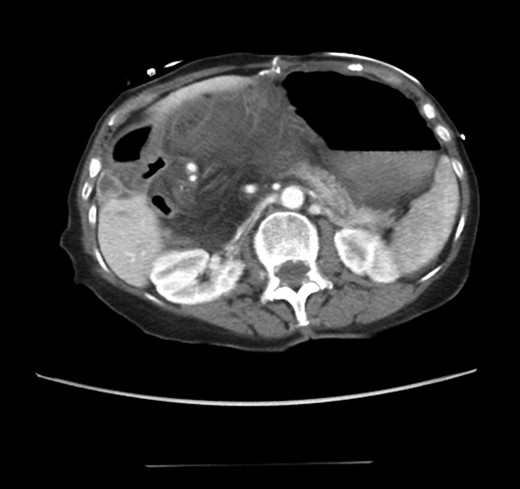

An 81-year-old female with a medical history of CAD with stents, hyperlipidemia, hypothyroidism, GERD, recent UTI, pancreatic cyst, constipation, anemia and leukopenia presented to the ED with a 1 day history of mild, diffuse and cramping abdominal pain. The patient was unable to give an accurate history, but the son at bedside supplemented this reporting that for several years the patient had been experiencing ill-defined abdominal discomfort. Physical exam showed a soft abdomen with mild tenderness and no evidence of peritonitis. A CT scan of the abdomen and pelvis with IV and PO contrast (Fig. 1) showed edematous changes to the mesentery of the small and large bowel with swirling of vessels indicative of internal hernia. The stomach was also noted to be distended with both air and fluid as a consequence of posterior compression by the hernia contents (Fig. 2). A surgical consult was obtained, a nasogastric tube and Foley catheter were placed, antibiotics were started, and the patient was taken for an exploratory laparotomy. Upon entering the abdomen through a vertical midline incision, 1.5 l of ascites was drained revealing a diffusely edematous mesentery. A large portion of the small bowel was seen to be herniated through the Foramen of Winslow (Fig. 3). A Kocher maneuver and division of the gastrocolic ligament were then performed to allow release of the herniated small bowel. It was at this time that, in addition to small bowel, a large portion of the ascending and transverse colon was noted to be herniated through the foramen of Winslow. The small bowel was also seen to be torsed about its own mesentery. Normal anatomy was restored and the bowel noted to be healthy and viable with peristalsis (Fig. 4). Due to the large size of the foramen after reduction and enlargement, it was deemed best to leave it open to prevent any further incarceration or strangulation. The abdomen was closed and the patient tolerated the procedure well. At a follow-up visit 2 months later, the patient had well-healed incisions, was doing well, tolerating a diet, and gaining weight appropriately.

Externalized abdominal contents shown to be pink and healthy bowel with some areas of ecchymosis in the transverse colon.